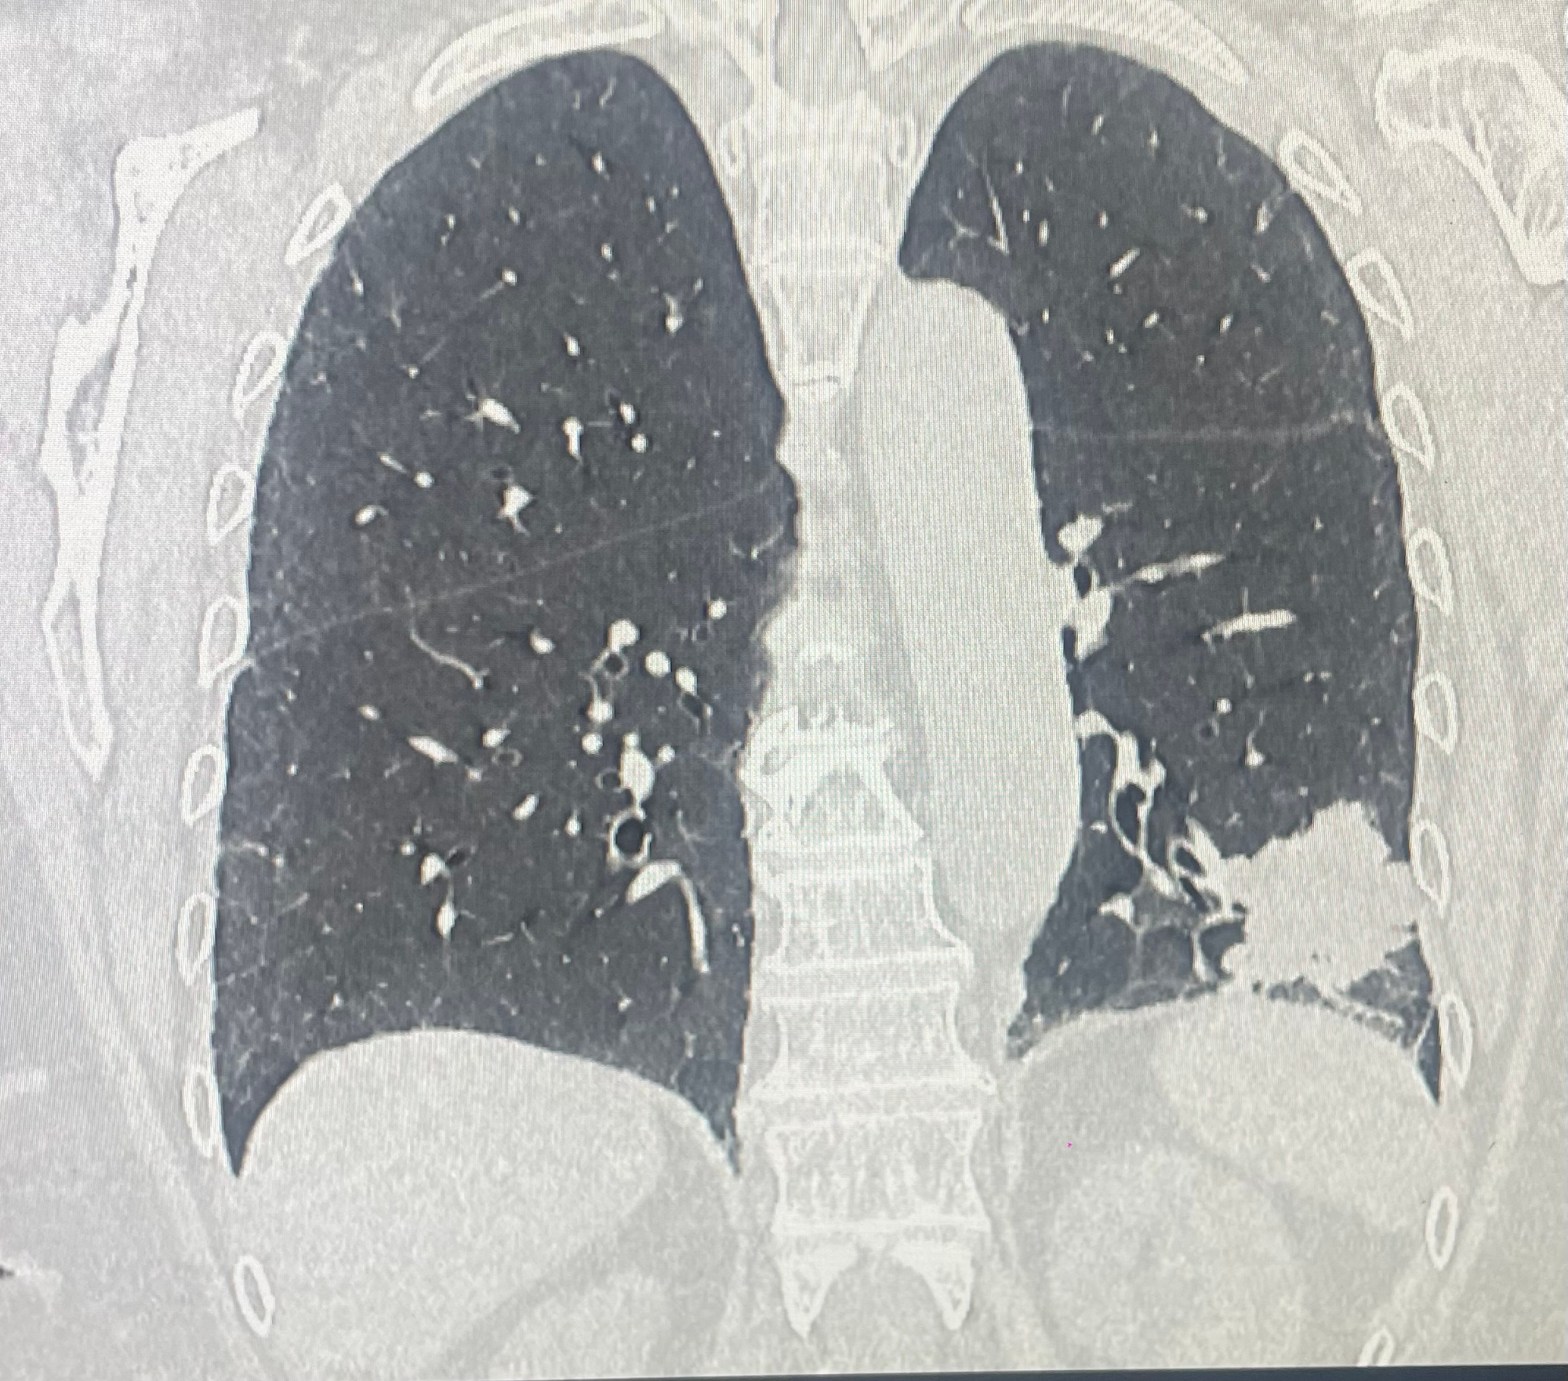

🤖Con tecnica robotica e’ stato asportato un segmento polmonare sede di metastasi da cancro della mammella